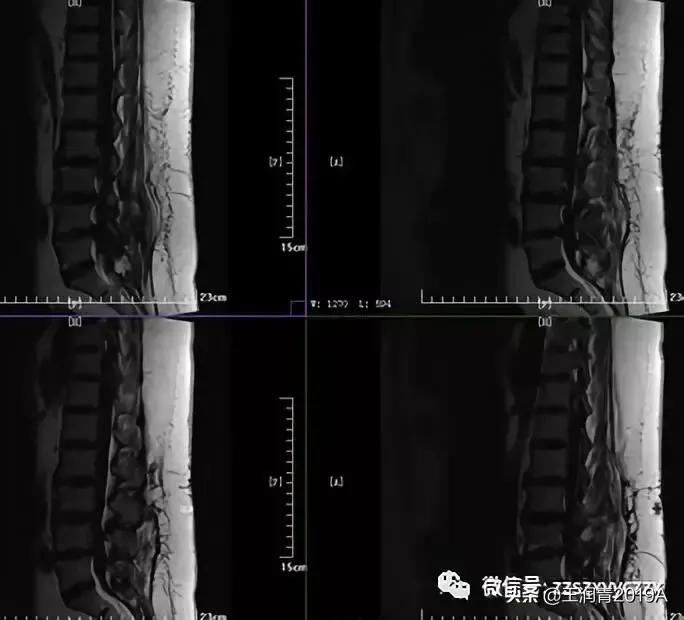

1、腰椎MR平扫检查(图2-3)

腰椎MRI:腰1-2、腰2-3、腰3-4、腰4-5及腰5-骶1椎间盘突出;平腰4椎体层面椎管内占位。